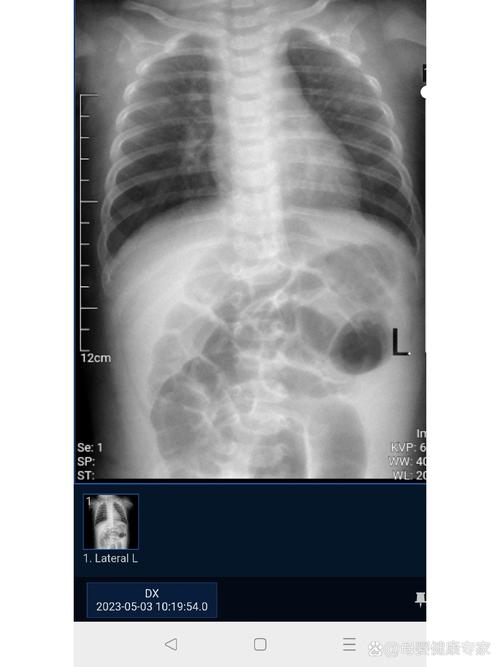

新生儿肺透明膜病的X线表现具有特征性,主要反映了肺泡萎陷、肺泡管和终末细支气管扩张以及支气管充气征的病理生理改变,其严重程度与病程进展密切相关,因此X线检查不仅是诊断的重要依据,也是评估病情和指导治疗的关键手段。

“白肺”

这是疾病发展到严重阶段的表现。

- 成因:肺泡萎陷范围极广,肺实质几乎完全失去气体,被渗出物(透明膜)和水肿液填充,肺动脉压力增高可能导致肺水肿,进一步加重肺实变。

- 特点:整个肺野呈均匀致密的白色,心影轮廓和膈面边缘变得模糊不清。支气管充气征可能仍然存在,是诊断的重要线索。

| II 级 (Grade II) | 肺野呈典型的“毛玻璃”样改变,支气管充气征清晰可见,心脏和膈肌轮廓尚可辨认。 | 中度HMD,通常需要CPAP或机械通气。 |

| III 级 (Grade III) | 肺野大部分呈“白肺”,支气管充气征非常明显,心脏边缘开始模糊。 | 重度HMD,需要强有力的机械通气支持。 |